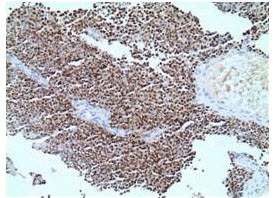

患者男,26岁,鼻腔肿瘤3个月,取活检,镜下显示如下图。

第1题,共3个问题

(多选题)对于发生于鼻腔的上述组织象的恶性肿瘤,需要鉴别的肿瘤类型包括()。

A:淋巴瘤

B:小细胞癌

C:嗅母细胞瘤

D:黑色素瘤

E:E.尤因肉瘤(Ewingsarcom

F:鳞状细胞癌

G:内翻性乳头状瘤

H:横纹肌肉瘤

第2题,共3个问题

(单选题)根据组织象及所给出的免疫组织化学染色MyoD-1,可以符合的诊断是()。(提示免疫组织化学MyoD-1见下图。)

E:尤因肉瘤(Ewingsarcoma)

第3题,共3个问题

(多选题)针对需要鉴别的肿瘤类型可选择的免疫标志物包括()。

A:LCA

B:Vimentin

C:Desmin

D:CD99

E:inhibin

F:CK

G:TTF-1

H:ER

I:HMB45